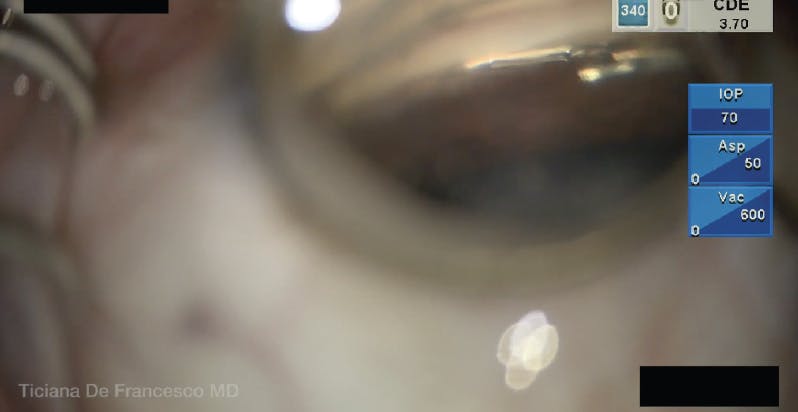

A 62-year-old patient with mild glaucoma presented with an IOP of 19 mm Hg on two classes of glaucoma medications. I planned to perform cataract surgery and implantation of the Hydrus Microstent (Alcon) in the patient’s right eye.

To begin the stent implantation, I placed the injector cannula into the anterior chamber and used a Swan Jacob goniolens to visualize the angle. I incised the inner wall of Schlemm canal with the distal tip of the cannula, which was positioned slightly superficially. As I attempted to deploy the Hydrus Microstent into Schlemm canal, I realized that part of the device was going into the suprachoroidal space.

I retracted the device into the injector cannula, pointed its distal tip slightly more upward, and attempted to redeploy the device. However, the stent again went into the suprachoroidal space, so it was retracted. I pointed the distal tip of the cannula farther upward and slowly deployed the device into Schlemm canal. At this point, the stent was correctly positioned, with its three windows in the canal (Figure).

Figure. Correct placement of the Hydrus Microstent is confirmed, with the three windows of the device in Schlemm canal.

To implant a Hydrus Microstent successfully, the distal tip of the injector cannula should be angled to around 30° upward while the inner wall of Schlemm canal is incised and the device is deployed. It is important to avoid incising the inner wall of the canal too superficially. Before deploying the stent, I relax my hand to minimize stress on Schlemm canal. Then, I slowly deploy the Hydrus while watching to confirm that the whole microstent is entirely positioned in the canal.